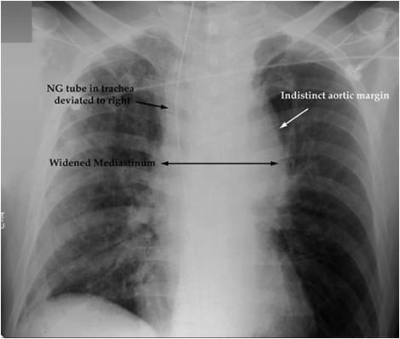

- צילום חזה: זמין ונדרש בכל חולה טראומה. הממצא האופייני ביותר הוא הרחבה של המייצר השכיח ב-85% מהחולים עם חבלה באבי העורקים (תצלום 18.16). סמנים נוספים מסוכמים בטבלה 8.16 (ראו בפרק הטיפול הראשוני בנפגע). בשבעה אחוזים מהחולים לא נראה כל ממצא בצילום חזה.

| טבלה 8.16: סמנים בצילום חזה לחבלה באבי העורקים | |

|---|---|

| Indistinct aortic knob | 24% |

| Lt. Pleural effusion | 19% |

| Apical cap | 19% |

| 1st/2nd rib fracture | 13% |

| Deviation of the trachea para-tracheal density | 12% |

| Deviation of esophageal to right (NG tube deviation) | 11% |

| Depressed Lt. Bronchus | 5% |